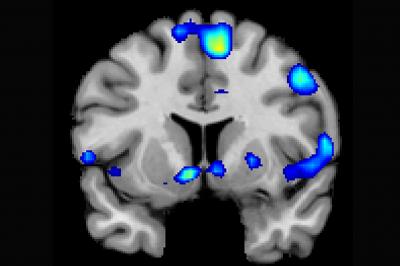

SALT LAKE CITY - Religious and spiritual experiences activate the brain reward circuits in much the same way as love, sex, gambling, drugs and music, report researchers at the University of Utah School of Medicine . The findings will be published Nov. 29 in the journal Social Neuroscience .

Based on fMRI scans, the researchers found that powerful spiritual feelings were reproducibly associated with activation in the nucleus accumbens, a critical brain region for processing reward. Peak activity occurred about 1-3 seconds before participants pushed the button and was replicated in each of the four tasks. As participants were experiencing peak feelings, their hearts beat faster and their breathing deepened.

In addition to the brain's reward circuits, the researchers found that spiritual feelings were associated with the medial prefrontal cortex, which is a complex brain region that is activated by tasks involving valuation, judgment and moral reasoning. Spiritual feelings also activated brain regions associated with focused attention.